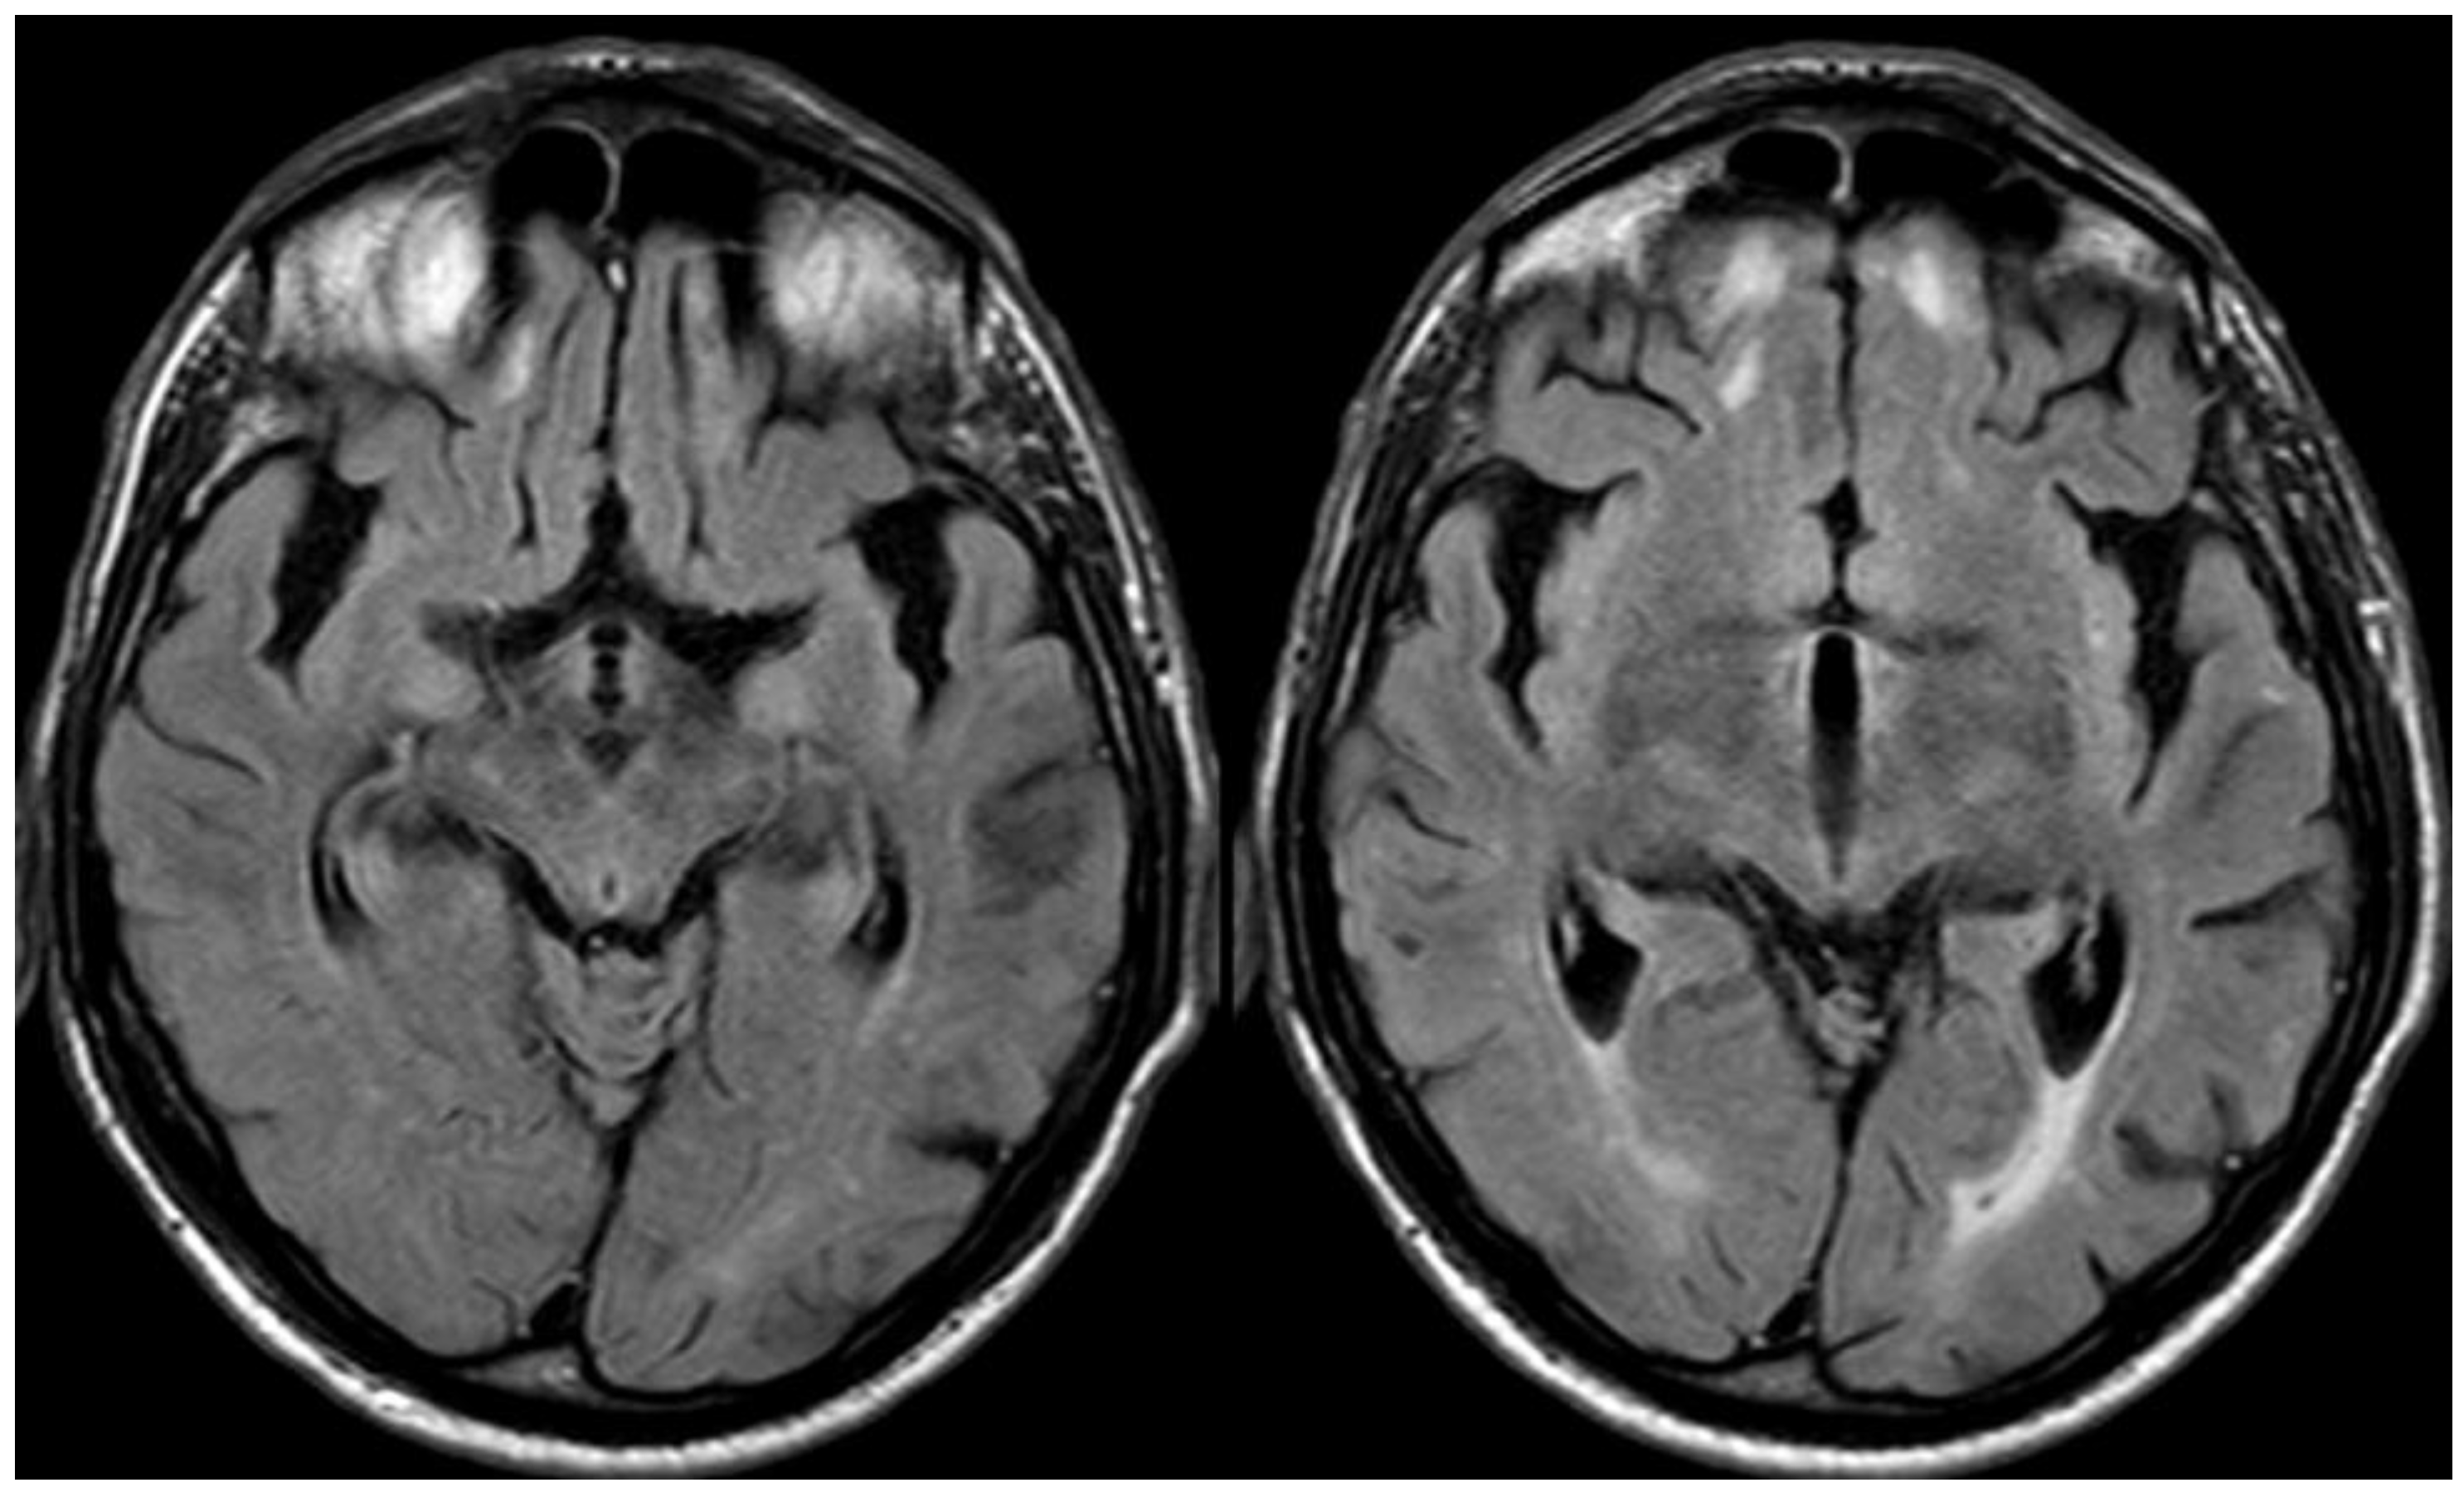

5. February 2017: First Recurrent CAA-Related Inflammation